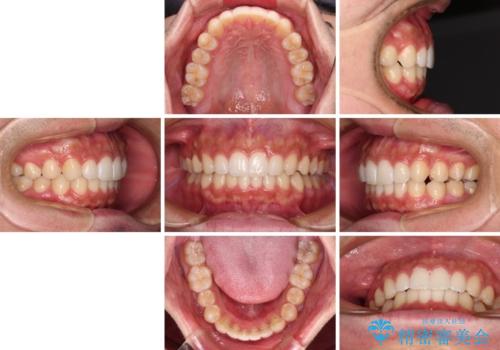

前歯のデコボコと突出感 インビザラインにて矯正治療

- 上下前歯のデコボコを気にして来院された患者様です。

インビザラインによる上下歯列の側方拡大と後方移動、IPR(歯と歯の間を削る)にるスペースの獲得により歯列を整えることとしました。

左上の小臼歯は捻転が強く、あえて180逆向きの状態で終了させる治療計画としました。

ご自宅と職場がともに遠方であったため、治療期間は長くなりましたが、患者様も我々も期待して以上に口元の突出感を改善することができました。